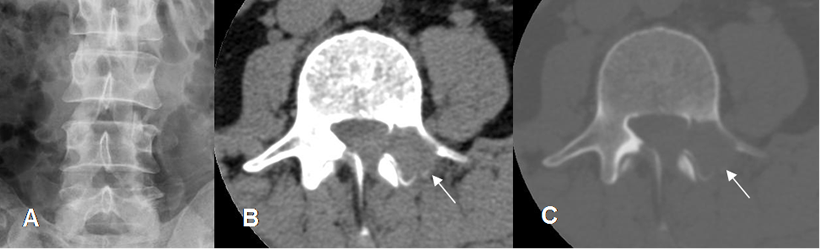

Fig 7 B. Tumor no visto en columna.

A: Rx AP. No se aprecian alteraciones.

B: TAC axial en ventana de tejido y C: TAC axial en ventana osea. Lesión lítica y expansiva en la lámina y el pedículo, no demostrada en la Rx simple.